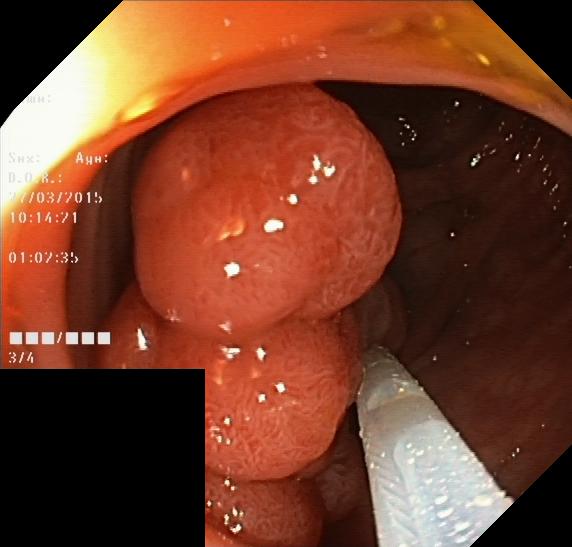

V Object detection

Object detection is the problem of recognising and locating any objects of interest in an image. In the context of GIE, the objects of interest may be polyps, tools, artefacts, or disease. In this section, we detail and present our evaluation of the fine-tuned performance of backbones in polyp detection specifically.

V-A Data

The data used in our object detection experiments is taken from the Kvasir-SEG dataset[45], which does not share any instances with Hyperkvasir-unlabelled. The dataset includes 1000 GIE images, each of which shows at least one polyp and is paired with both a set of bounding boxes, specifying the location and the horizontal and vertical dimensions of any polyps in the image, and a binary segmentation map indicating which pixels correspond to a polyp and which don’t. While the segmentation maps were used in our semantic segmentation experiments, here we use the sets of bounding boxes. We applied a random 80%/10%/10% training/validation/test split, where the validation data is used to determine whether to save the weights after each epoch of training on the training data, and the test data is reserved for evaluating the model after fine-tuning.